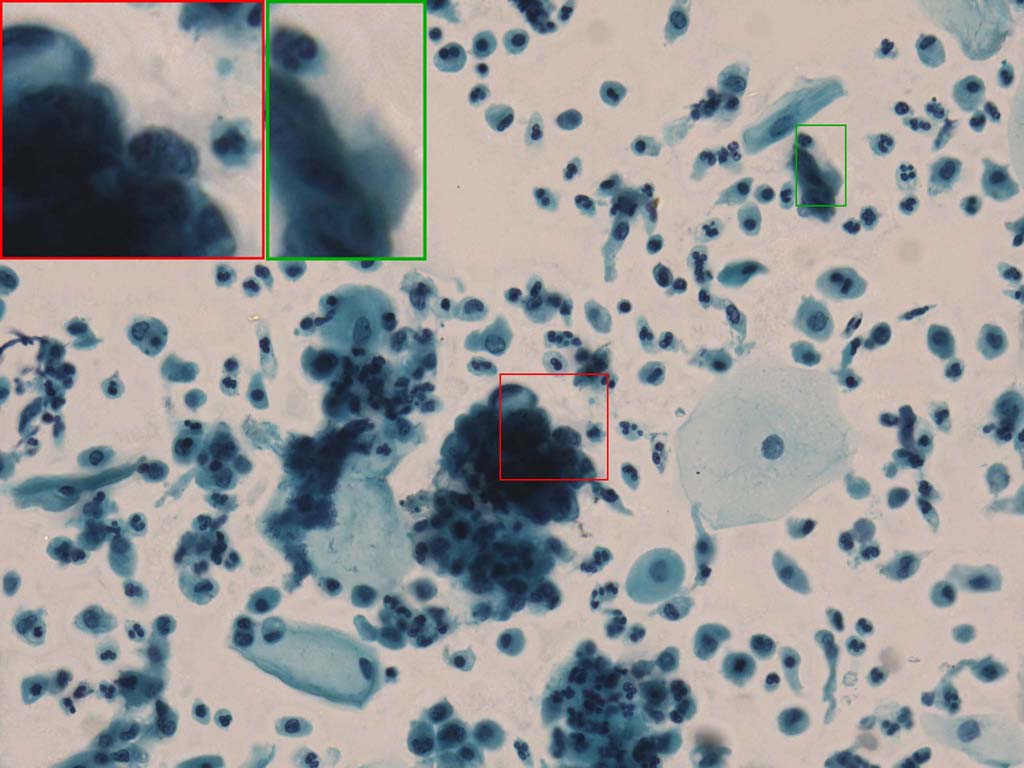

A good image fusion method should contain the following properties. First, it preserves both the details of small size objects and the integrity information of large size objects in the fused image, even in the case of the size of the interested objects varying largely in the image. For example, the cervical cell images from the microscope contain both small size isolated cells and large size agglomerates, which are both useful for cervical cytology [5]. Second, it should be efficient enough to handle large-scale data. For instance, it needs to process thousands of fields of view (FoV) in an acceptable time for the whole slide scanning in digital cytopathology [6], which requires to fuse a series of high resolution images captured at each FoV in a very efficient way. Third, it does not produce obvious artifacts. Despite being studied extensively, to our best knowledge, existing fusion methods may not meet these requirements simultaneously.

To demonstrate the effectiveness and efficiency of the proposed image fusion method , we conduct a set of comparative experiments on three image datasets. The first is composed by 8 pairs of multi-modal medical images and the second one contains 15 pairs of multi-focus gray or color natural images. These two datasets are often used in many related papers and some examples are shown in Figure 3(a) and Figure 3(b). The third one is a new multi-focus cervical cell image dataset collected by ourselves, which consists of 15 groups of color images and each group contains a series of multi-focus cervix cell images with size of or , etc. Some source examples are shown in Figure 3(c). Our source code implemented in C++ along with the new multi-focus cervical cell image dataset is available online.

Figure 9, Figure 10 and Figure 11 show the comparative fused results of the multi-focus cell images shown in Figure 3(c). For clarity, we also present a closeup view in the right-bottom of each sub-picture in Figure 9 and Figure 10. As shown in the close-up views of Figure 9, the fused images based on DSIFT, IM, MWGF and BF methods are extremely blurred in the boundary and fail to keep the details of cell nucleus. Furthermore, the DTCWT and NSCT based methods produce halo artifacts in the fused images, while GFF and CNN based methods fail to preserve the small cell nucleus. LP-SR based method nearly works fine which keeps the most of the details of the small size cells, but the integrity of the clustered large size cells is damaged. Fortunately, in our proposed method, the integrity of the clustered large size cells is preserved and most of the isolated small size cells are maintained from the original images, which demonstrates the best visual quality.

Similarly, as shown in the close-up views of Figure 10, the fused images from DSIFT, IM, MWGF and BF are blurred and lose some nucleus details, while the results from DTCWT, GFF, CNN and NSCT produce halo artifacts. LP-SR based method can keep details well but also produces halo artifacts and other noise. Our method can preserve the focused areas of different source images well without introducing any artifacts. For the example illustrated in Figure 11, the fused images generated by DSIFT, DTCWT, IM and NSCT all fail to preserve the focused areas of different source images and result in extremely blurred images. The GFF, CNN, MWGF and BF based method introduces a lot of color distortion of the nucleus regions and the obvious halo artifact. The result of LP-SR based method is close to the one of our method but introduces some odd color distortion. Again, our method produces fused image which can preserve the focused areas of different source images well without introducing any artifacts.